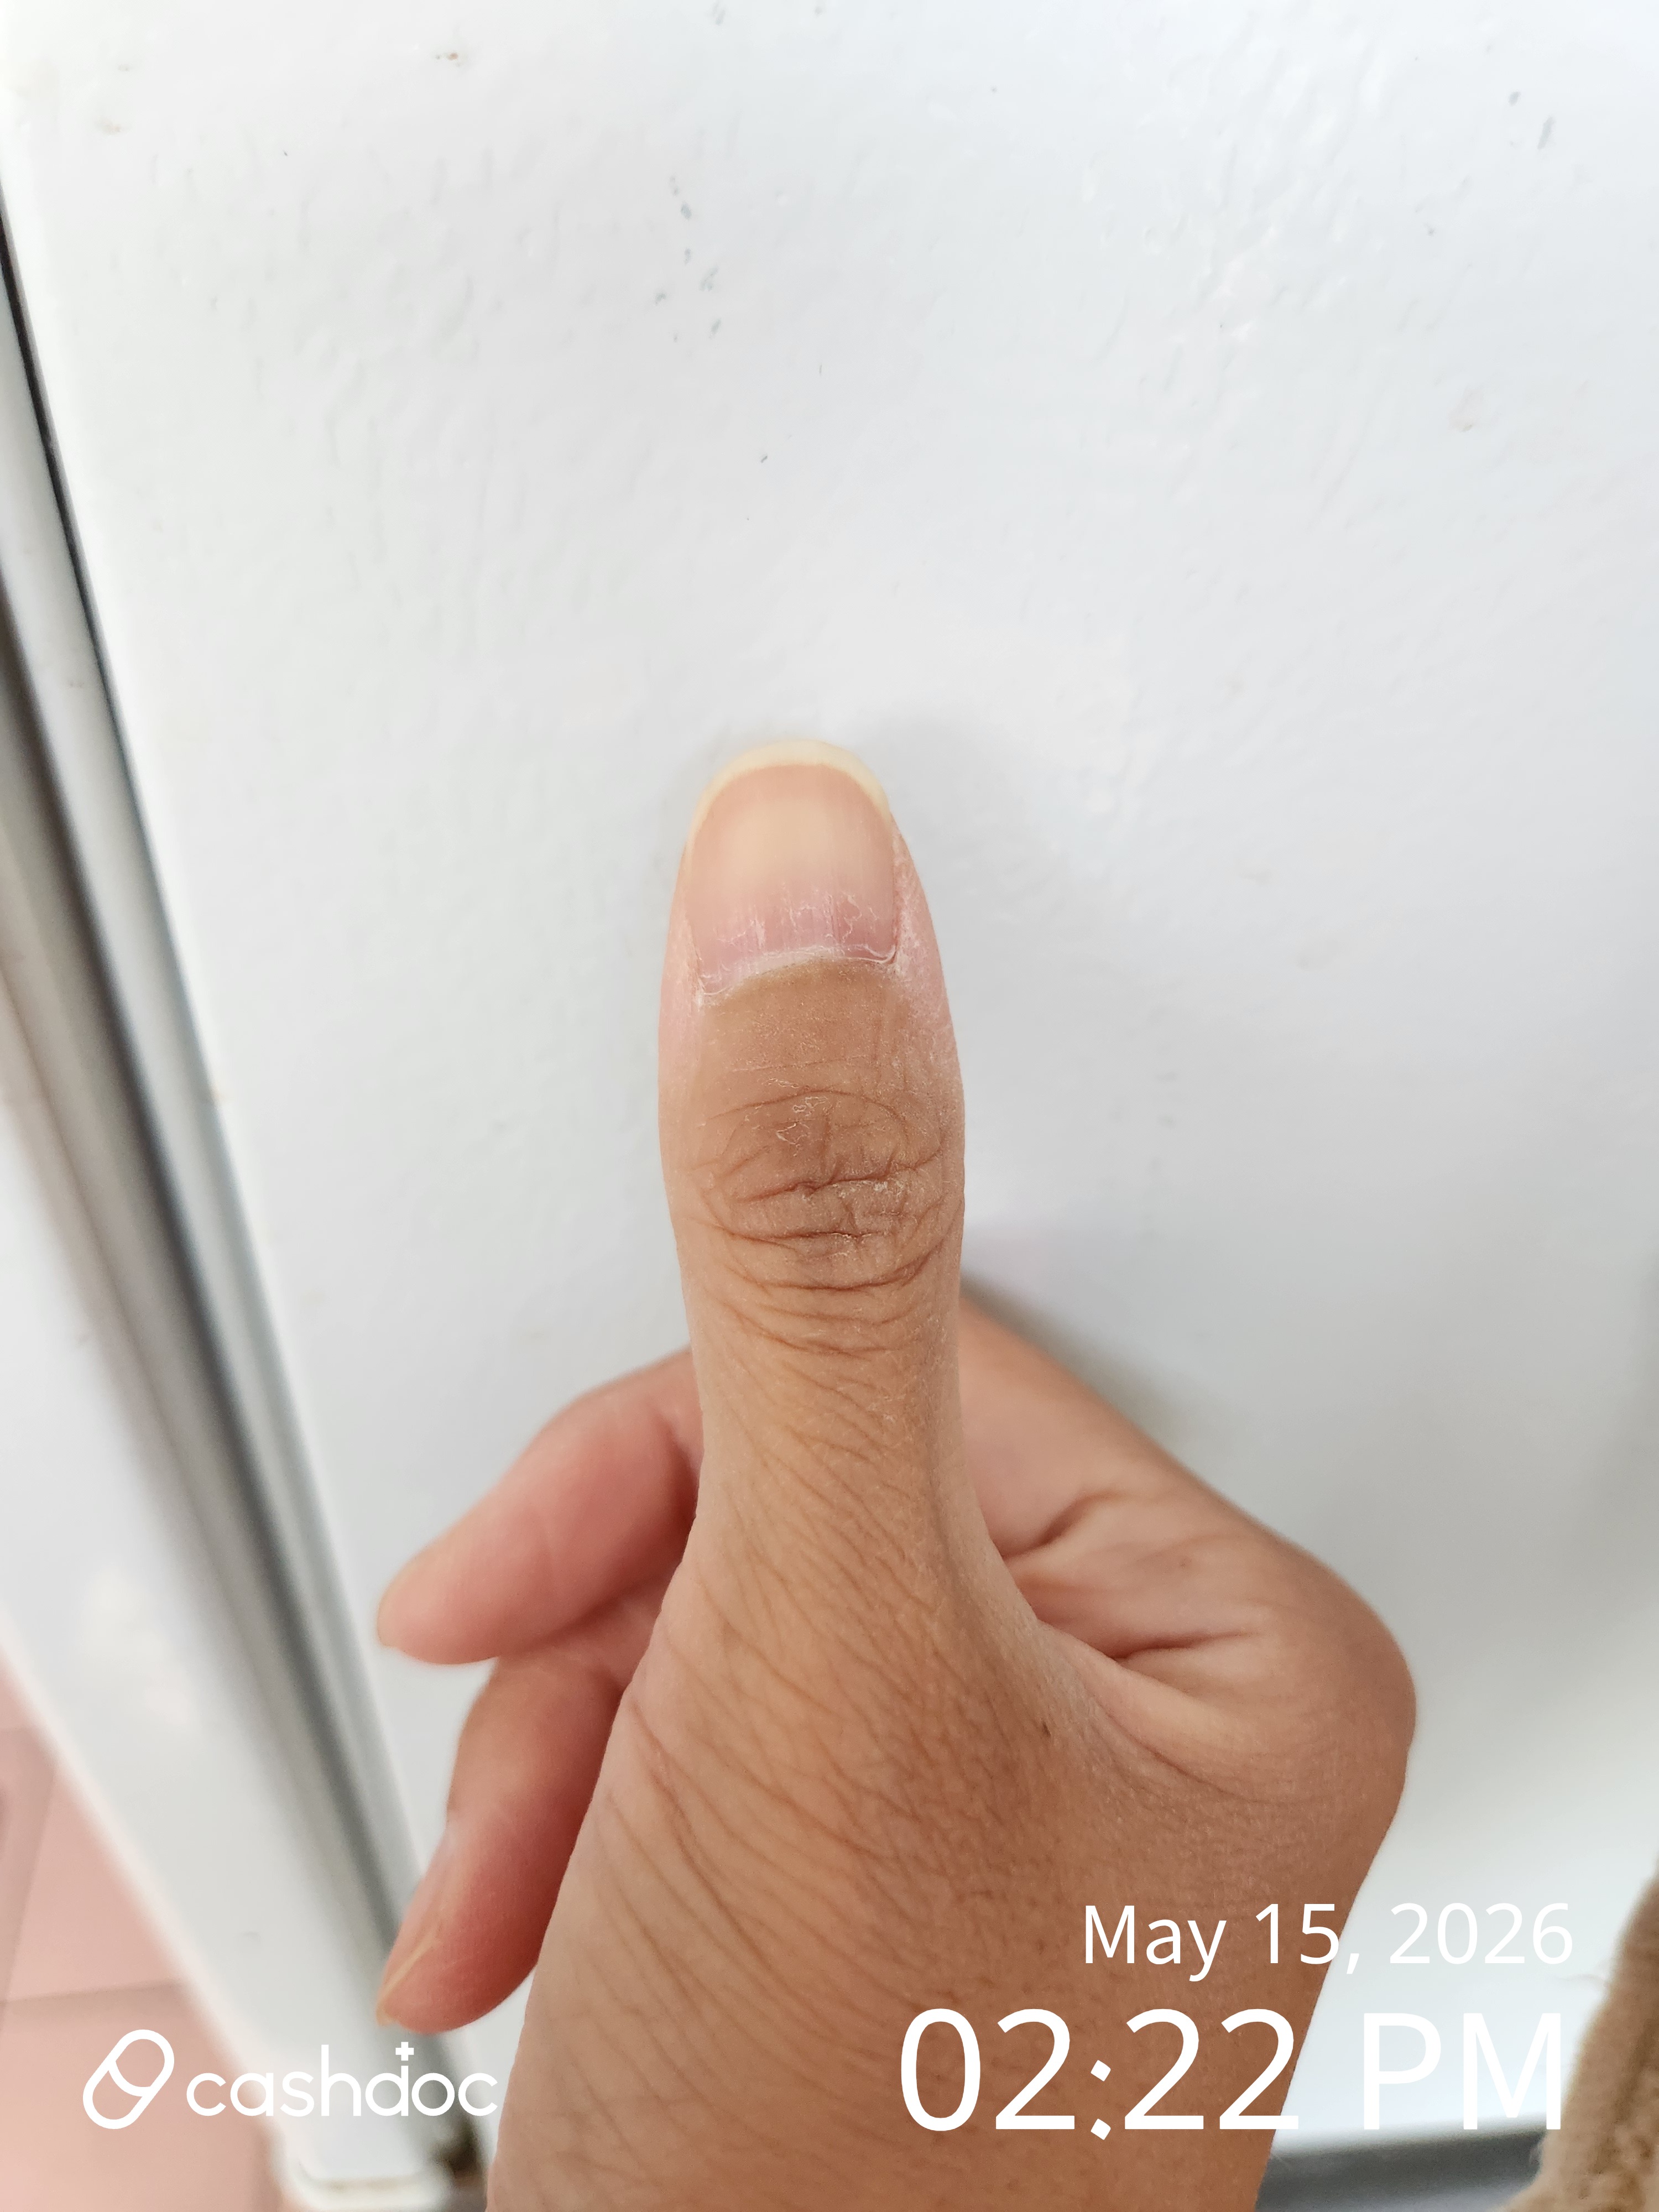

발목 퇴행성관절염. 당당의사선생님. 허정태선생님의진료로 꾸준하게 치료중 입니다 거의2년. 정도의치료로서 효과적 이었습니다. 가끔씩. 물리치료를 하고요. 효능과 편안하게 느껴지는 것은. 치료잘받고 있습니다. 먹는약으로도. 효과적인 방법 인것으로 느껴지는 것입니다

발목 퇴행성관절염. 당당의사선생님. 허정태선생님의진료로 꾸준하게 치료중 입니다 거의2년. 정도의치료로서 효과적 이었습니다. 가끔씩. 물리치료를 하고요. 효능과 편안하게 느껴지는 것은. 치료잘받고 있습니다. 먹는약으로도. 효과적인 방법 인것으로 느껴지는 것입니다